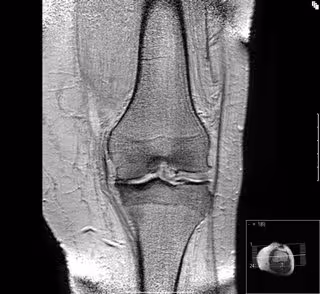

Expertos investigan cómo combinar células y materiales para regenerar el cartílago de las articulaciones

Artrosis de rodilla

Un proyecto de la Universitat de València (UV), la Universitat Politècnica de València (UPV) y el Instituto de Investigación Sanitaria Incliva investigan cómo combinar células y materiales para regenerar el cartílago de las articulaciones.

Carmen Carda explica, en un comunicado, que las lesiones en las articulaciones son frecuentes en jóvenes y en adultos de edad media, y aunque no son especialmente graves, sí son molestas e invalidantes. Actualmente los cirujanos cuentan con escasas herramientas para tratarlas.